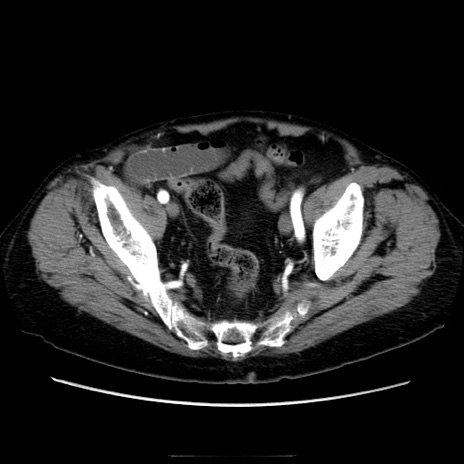

症例21(横断像)

【症例】70歳代男性

【主訴】腹痛

【現病歴】肝硬変・肝細胞癌にてかかりつけの方。約9時間前に食後より腹痛出現。症状が徐々に増悪し、嘔吐出現したため来院。

【既往歴】肝硬変、肝細胞癌(RFA、TACE後)

【身体所見】意識清明、表情苦悶様、BT 36℃、BP 129/78mmHg、P 88bpm、SpO2 97%(RA)、右上腹部から心窩部にかけて圧痛あり、反跳痛なし、筋性防御あり。

【データ】WBC 5800、CRP 0.16